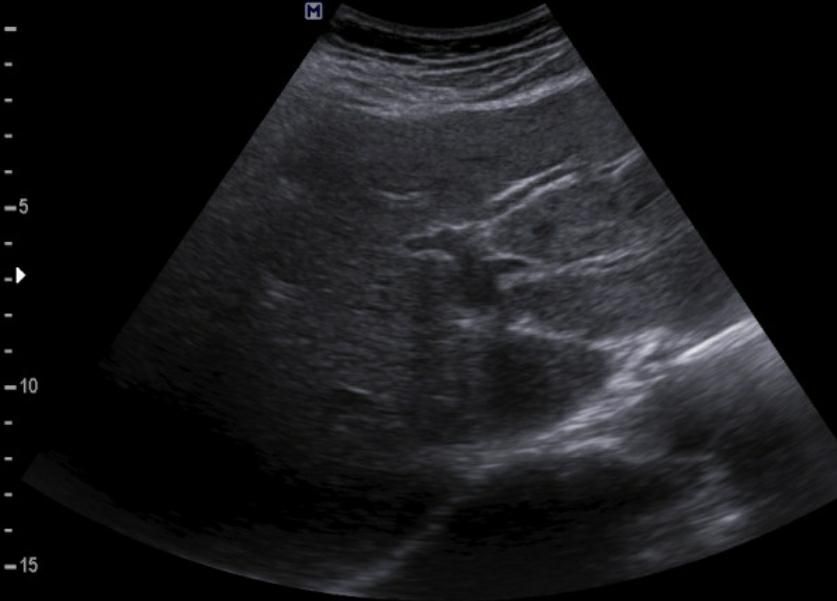

간에 혹이 있는건가요? 초음파 사진 봐주세요

간에 혹이 있는건지 맞다면 크기나 모양이 혈종인지 아이면 암으로 의심이 되는지 초음파 사진 봐주세요...ㅜㅜㅜ꼭 답변 부탁드립니다

• 1번 째 사진

간 초음파로만 봐서는 약간의 지방간이 관찰되지만 혈종으로 의심되지는

않으며 사진 우측에 보이는 동그란 부분은 장의 단면이 관찰되었을 가능성이

높은 것으로 보입니다